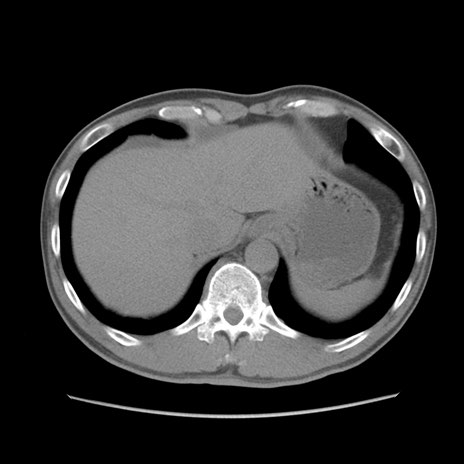

症例56 CT(横断像)

脂肪ウインドウ